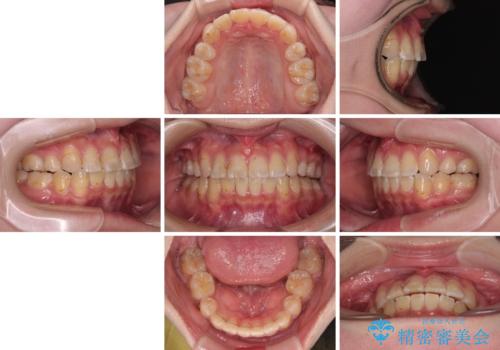

転位歯や埋伏歯などの難易度の高い抜歯矯正治療

- 八重歯や埋伏している奥歯など、多くの難しい問題を抱えている患者様です。

重度叢生のため、大臼歯をしっかりと咬合させるために、下顎は左右第二小臼歯を、上顎は前歯部の叢生を解消するために左右第一小臼歯を抜歯し、口元の突出感を改善するために、上顎大臼歯が前方に移動しないようにするために、補助装置による架強固定を行うこととしました。

叢生は思ったよりも早期に改善されましたが、舌の突出癖による上下前歯の非接触が全く改善されず、2年間ほど治療期間が延びる結果となってしまいました。